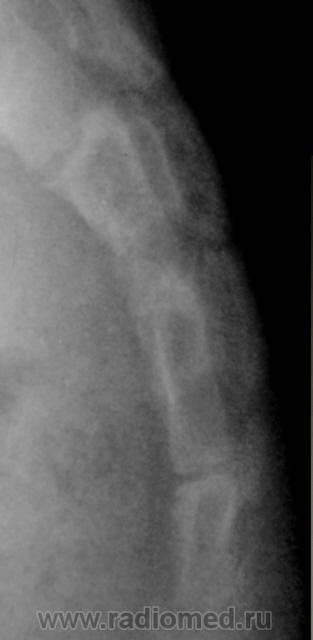

Ребенок направлен хирургом на рентгенографию крестца и копчика, Накануне ребенок упал. Приводится только боковая рентгенограмма, так как рентгенограмма, выполненная в прямой проекции не информативна.

Вопрос. Есть перелом или нет перелома?

Перелома нет

Уважаемый Валентин Львович! Наличия костно-травматических изменений со стороны объекта исследования не выявлено. Кстати, у меня редко получаются такие красивые рентгенограммы крестца и копчика.

Валентин Львович! Мне видится межпозвонковый промежуток. Смещение по ширине отсутствует. Возможно такой вариант развития. Все таки изолированно сломать крестец у ребенка сложно.

Я тоже костно-травматических изменений не вижу.

Согласен с Ермолаевым, это межпозвонковый промежуток.